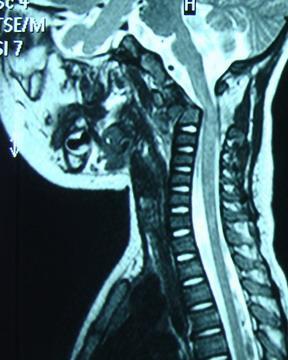

枢椎齿突骨折(odontoid process fracture)是累及寰枢椎区域稳定性的严重损伤,发生率约占颈椎损伤的10%。由于具有特殊的解剖学结构,其不愈合发生率也较高,不稳定性因素的存在,可能导致急性延迟性颈椎脊髓压迫并危及生命。